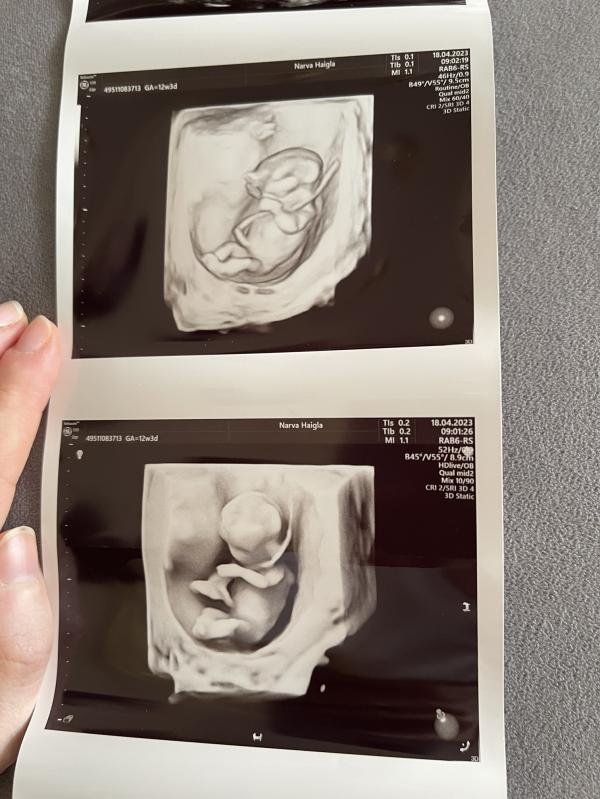

Мы тоже были сегодня на узи🥰

Развиваемся хорошо,все прекрасно работает,токсикоз пока еще есть.

Пдр-28 октября🌸

@natalja.klink, конечно 😀 эти принцессы просто прячутся😁 в этот раз нечто нечёткое есть с 13 недель, не такое классное как у тебя 😀 а в прошлый раз у меня есть одна фотка, с узи в Пуру в 29 недель, тут ни разу не смогли сделать